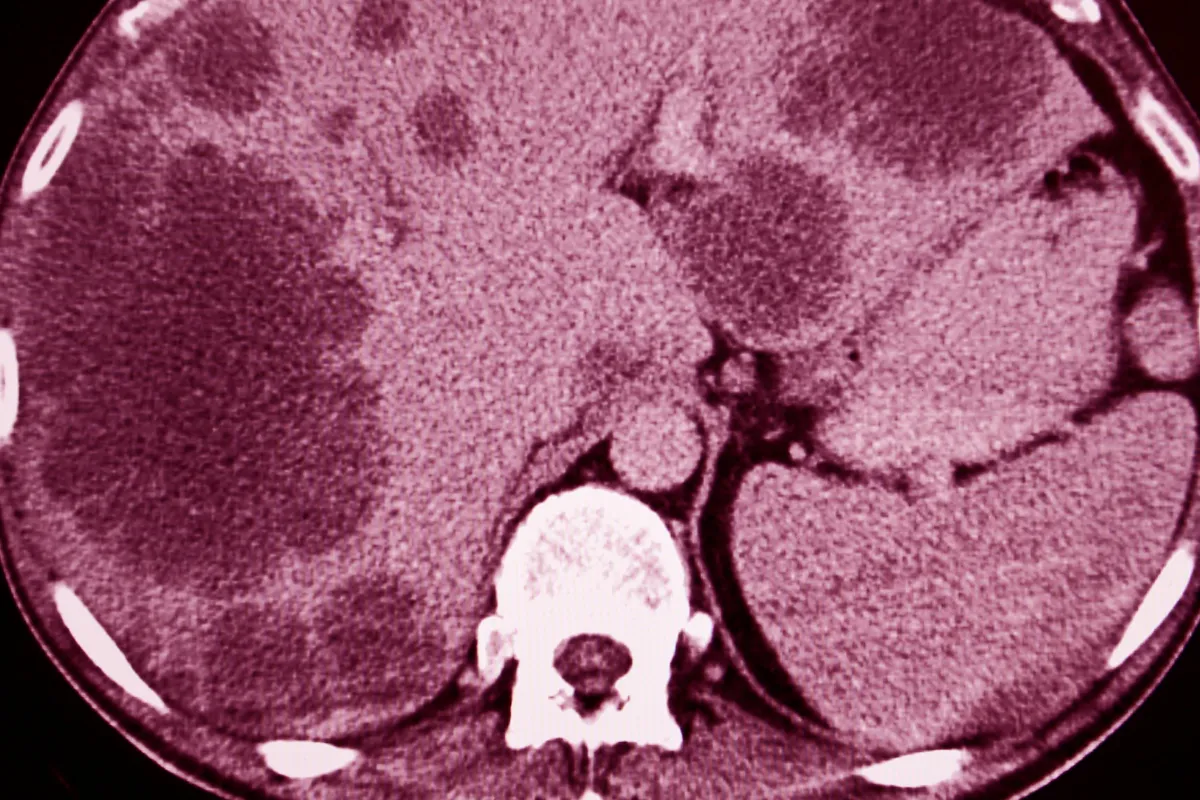

A precise cancer diagnosis is essential for creating an effective treatment plan. The process begins with a physical exam and a review of medical history. While imaging tests like CT scans, MRIs, and PET scans provide images of a tumor’s size and location, a biopsy is the definitive diagnostic tool. This involves removing a small tissue sample for a pathologist to examine. Blood tests may also be used to detect tumor markers. This collective data is then used to “stage” the cancer, a critical step that determines the extent of the disease.

• Imaging Tests: CT, MRI, and PET scans produce detailed images of organs and tissues to detect tumors and measure their size.